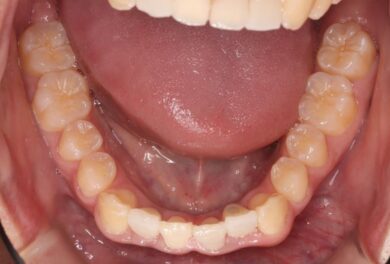

下顎の前歯は通常6本ですが、中央から2番目の歯(側切歯)が左右2本とも欠損している先天性欠如の患者様です。

初診時、下顎だけでなく、上顎の正中(真ん中)にも空隙(隙間)がありました。

• 治療前